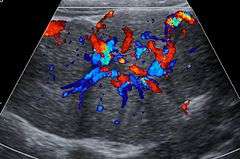

Focal nodular hyperplasia (FNH) is a benign tumor of the liver (hepatic tumor), which is the second most prevalent tumor of the liver (the first is hepatic hemangioma). It is usually asymptomatic, rarely grows or bleeds, and has no malignant potential. This tumour was once often resected because it was difficult to distinguish from hepatic adenoma, but with modern multiphase imaging is usually now diagnosed by strict imaging criteria and not resected.

Focal nodular hyperplasia's most recognizable gross feature is a central stellate scar seen in 60–70% of cases. Microscopically, a lobular proliferation of bland-appearing hepatocytes with a bile ductular proliferation and malformed vessels within the fibrous scar is the most common pattern. Other patterns include telangiectatic, hyperplastic-adenomatous, and lesions with focal large-cell dysplasia.[1] Rarely, these lesions may be multiple or can occur as part of a syndrome with hemangiomas, epithelioid hemangioendothelioma, hepatic adenomas, fibrolamellar hepatocellular carcinoma, vascular malformations of the brain, meningiomas, and/or astrocytomas.[1]

FNH is not a true neoplasm; it is believed to result from localized hyperplastic hepatocyte response to an underlying congenital arteriovenous malformation. It consists of normal liver constituents in an abnormally organized pattern, grows in a stellate pattern and may display central necrosis when large.[2] Additionally evidence suggests that the incidence of FNH is related to oral contraceptive use.[3]